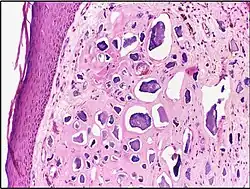

![]() | Fat necrosis | Breast lump showing an area of fat necrosis showing shadowy outlines of necrotic adipocytes surrounded by an inflammatory reaction with cholesterol clefts. | Category: Histopathology of liponecrosis | Liponecrosis |